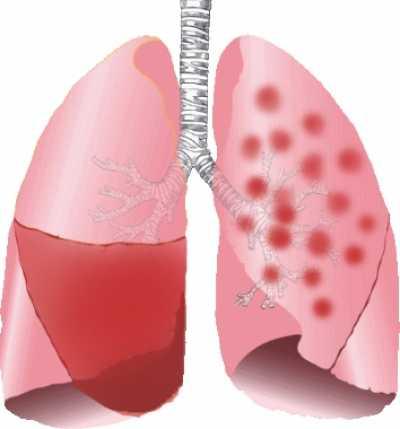

Der Heilungsprozess bei einer Lungenentzündung kann je nach Schweregrad und individuellem Gesundheitszustand unterschiedlich lange dauern. In den meisten Fällen ist die Pneumonie innerhalb von zwei bis drei Wochen überstanden, sofern keine Komplikationen auftreten. Es ist jedoch wichtig zu beachten, dass sich die Genesung verzögern kann, wenn es zu Entzündungen des Rippenfells, Eiteransammlungen in der Lunge oder anderen Komplikationen kommt.

In einigen Fällen kann die Genesung von einer Lungenentzündung durch verschiedene Komplikationen verzögert werden. Eine Entzündung des Rippenfells oder Eiteransammlungen in der Lunge (Abszesse) können den Heilungsprozess beeinträchtigen und zu einer längeren Krankheitsdauer führen. Es ist wichtig, dass solche Komplikationen frühzeitig erkannt und behandelt werden, um die Genesung zu unterstützen.

In einigen Fällen können Komplikationen auftreten, die die Genesung verzögern können. Eine Entzündung des Rippenfells oder Eiteransammlungen in der Lunge (Abszesse) sind Beispiele für solche Komplikationen. Wenn solche Komplikationen auftreten, kann die Erholungszeit länger sein und eine spezielle Behandlung erfordern.

In einigen Fällen können Komplikationen auftreten, die die Genesung verzögern können. Zum Beispiel kann es zu einer Entzündung des Rippenfells kommen oder Eiteransammlungen in der Lunge (Abszesse) können sich bilden. Diese Komplikationen erfordern eine zusätzliche Behandlung und können die Erholungszeit verlängern.